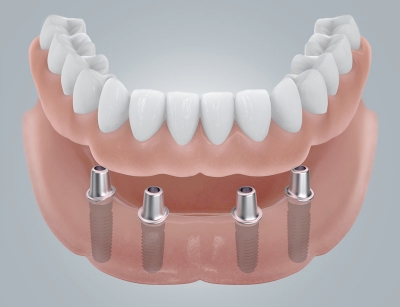

Самым современным способом восстановить безвозвратно утраченный зуб считается имплантация. При этом корень заменяется особой формы стержнем, вживляемым прямо в кость челюсти, а вместо коронковой части устанавливается на стержень искусственная коронка.

В случае полной адентии (отсутствия всех зубов на обеих челюстях), люди со съемными протезами могут заменить их на более комфортные – постоянные. Они прочно крепятся с помощью специальных переходников на имплантаты.